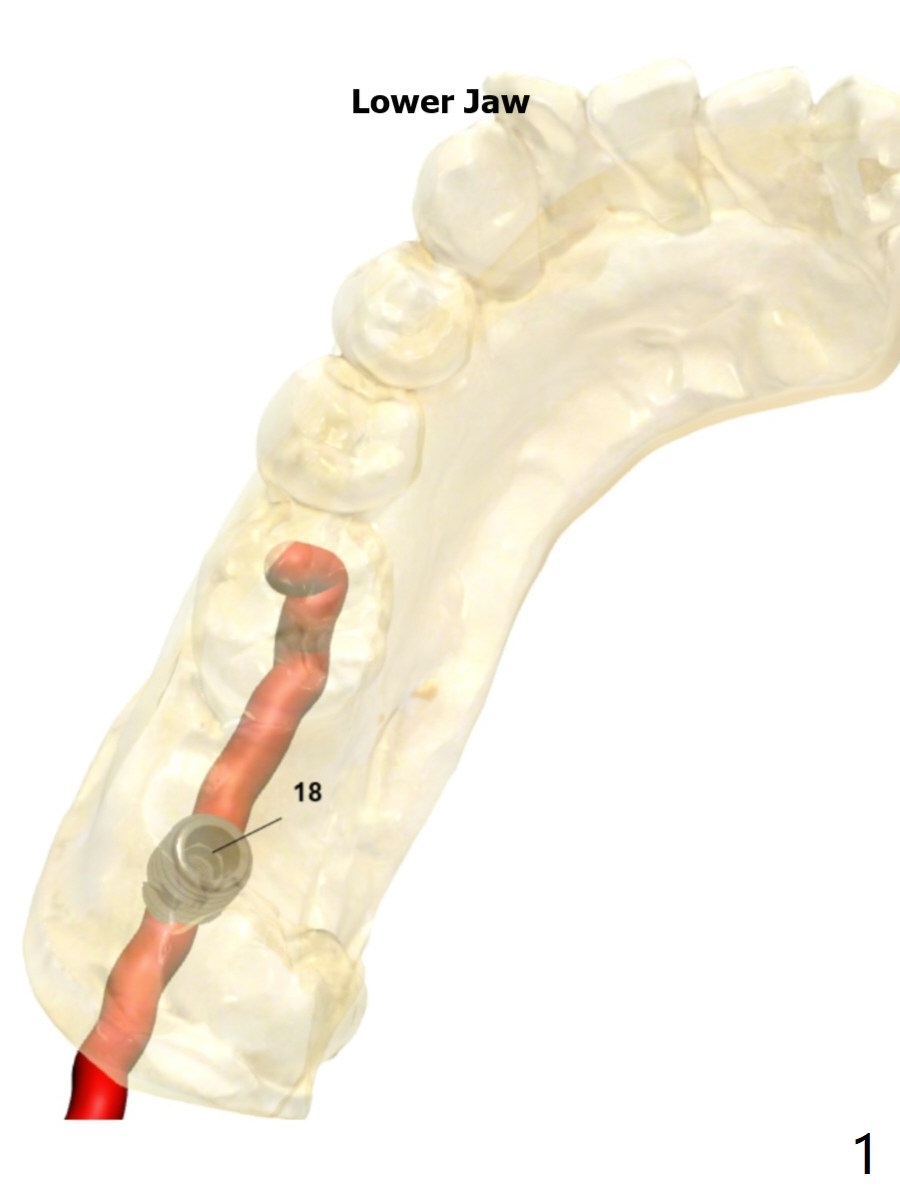

5x7.3 mm Implant with Sticky Bone   M

The tooth #17 will be extracted after guided surgery.

Return to Lower Molar Immediate Implant, Trajectory II

Xin Wei, DDS, PhD, MS 1st edition 09/09/2019, last revision 02/02/2020